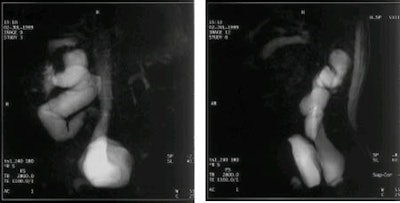

Así, en marzo de 1999, cuando el Centre Hospitalier Intercommunal de Cornouaille adquirió un aparato de resonancia magnética Magnetom Harmony 1T (de Siemens Medical Solutions, Iselin, NJ, EE.UU.), Rivoal y un técnico radiólogo pusieron una cucharadita de mermelada de arándanos en un vaso de agua y obtuvieron una imagen de RM. La doctora manifestó que ambos se sorprendieron al descubrir que la hiperseñal del agua era totalmente negativa.

La investigación del grupo reveló que el zumo de arándanos es por naturaleza rico en manganeso (Mn++), a 30 mg por litro. También produjo una hiperseñal (contraste positivo) en imágenes con secuencia ponderada en T1 y una hiposeñal (contraste negativo) en imágenes con secuencia ponderada en T2. Los investigadores posteriormente definieron un protocolo de estudio de imagen con zumo de arándanos.